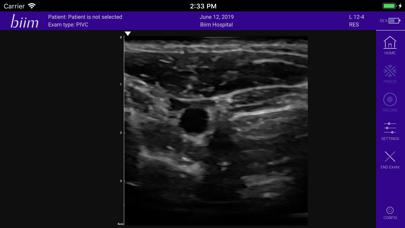

Biim Ultrasound

L5 | Needle Tip 18G Scanning Video | Wireless Ultrasound Transducer for iOS